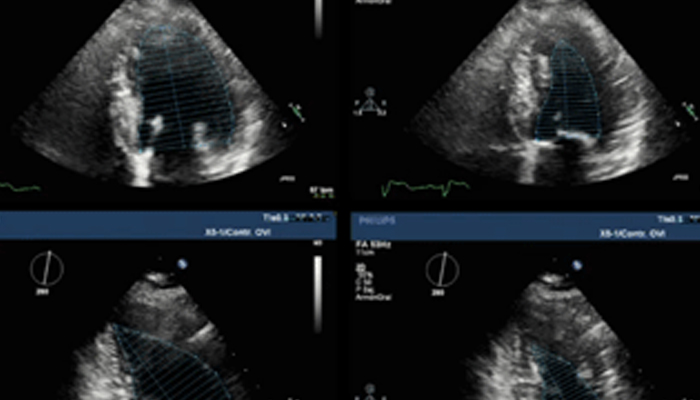

تشهد حاليًا خيارات العلاج التي لا تتطلب سوى تدخل جراحي محدود في القلب والأوعية الدموية انتشارًا ملحوظًا. ولقد ساهمت التطورات الأخيرة في مجالات التشخيص والتوجيه بالصور المباشرة Live Image Guidance والمعلوماتية في جعل هذا الأمر ممكنًا. بالتعاون مع أشهر أطباء أمراض القلب، ابتكرنا حلولاً تساهم في منح المرضى الفرصة لتغيير حياتهم. فهذه الحلول تساعد في تسريع سير العمل وزيادة فعالية الطاقم الطبي وتوفير أفكار سريرية.

تعلّم كيف تستطيع الحلول التي ابتكرناها في مجال طب القلب مساعدة مؤسستك